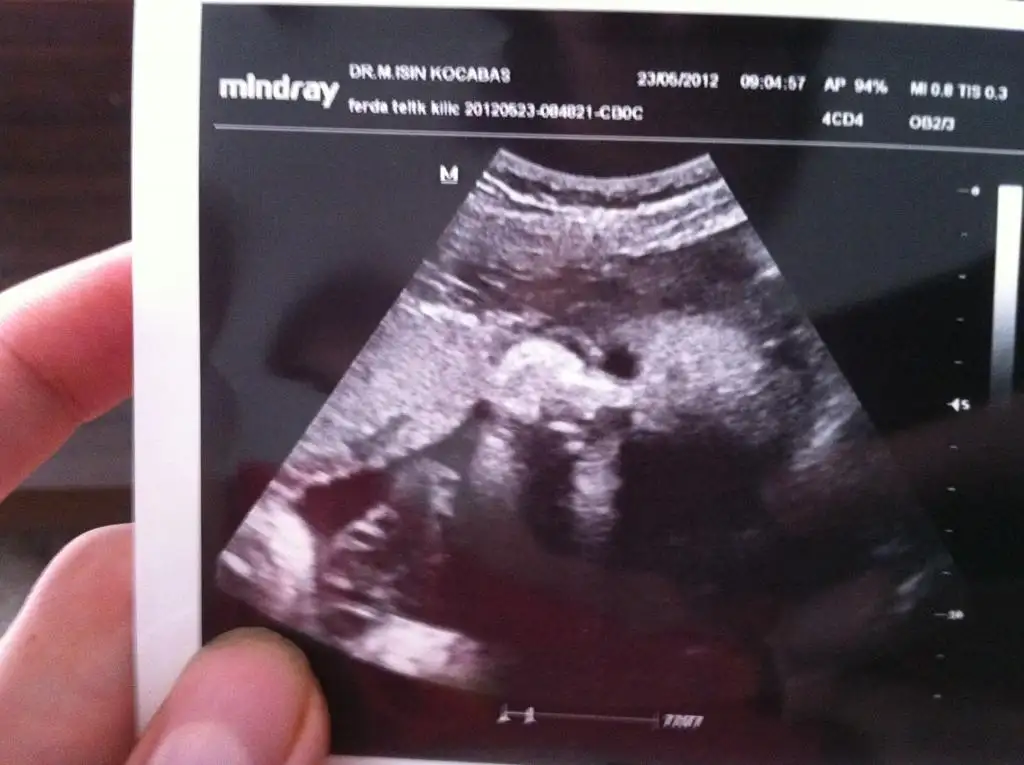

yüzünü gördük kaç haftadan sonra, fındık gibi bişey

resmini alalım mı dedim

hemen 3 boyutluyu açtı, rahat 10 dakika uğraştı ama görüntü yakalayamadı

hocam tamam önemli değil dedikçe hırslandım gösterecem dedi

siyah beyaz fotosunu alabildik, pek net değil ama ekleyim yine de

belki de gördüğümüz son fotosu olur

Eki Görüntüle 425660